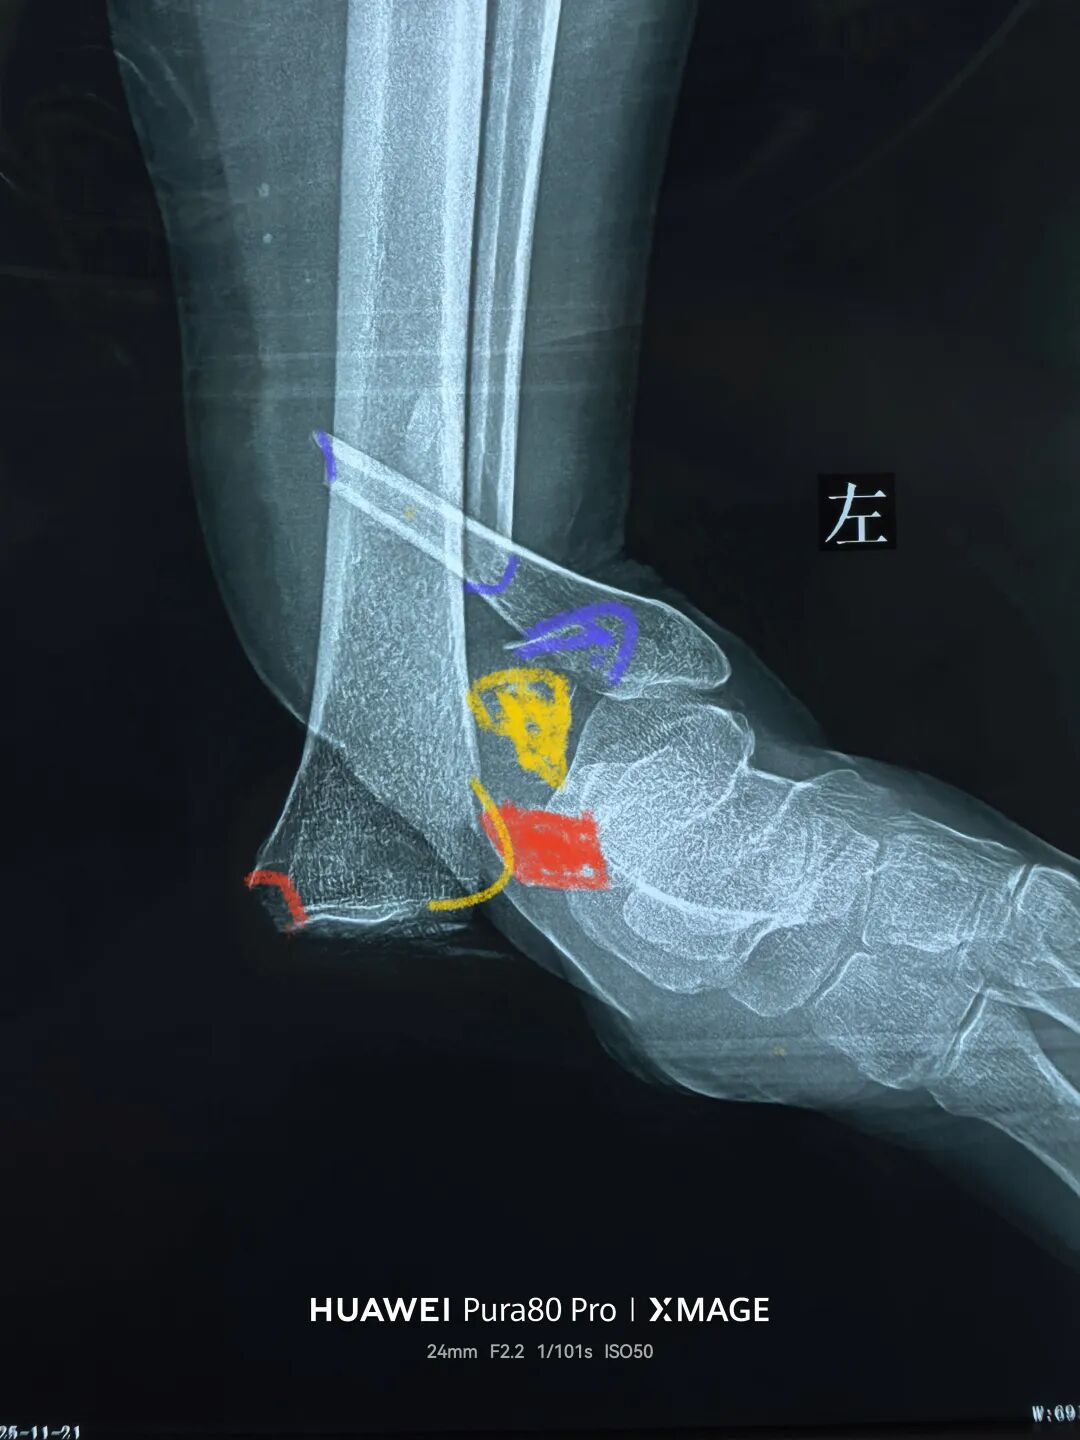

解剖复位

最后做下胫腓

两个位置螺钉固定

下胫腓关节复位

内踝间隙恢复

踝关节被动活动良好

期待切口和功能的恢复